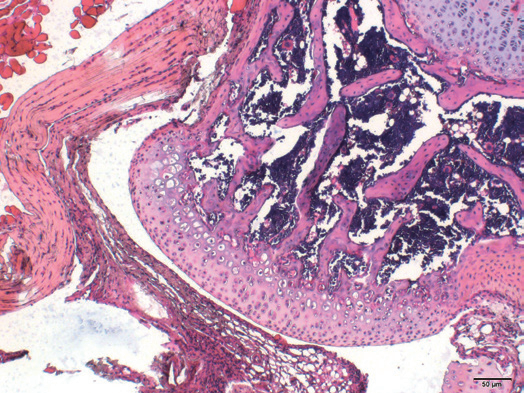

一、病理常规染色及特染项目

天狼星染色vs股骨病理分析

肿瘤病理分析VS心脏组织Masson染色

尼氏染色VSMallory染色

HEvs组织硬切

番红快绿

病理常规染色及特染项目